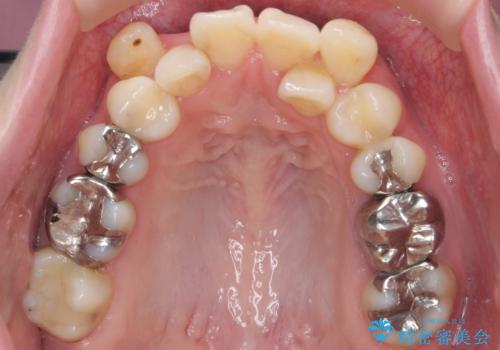

八重歯の部分は抜歯し、奥に入っていた前歯を前に移動させました。

下の前歯は生まれつき3本だったため、さらに2本下を抜くとなると3本少なくなってしまうため、下の前歯を一本お取りして最小限の抜歯としました。

上にはワイヤー部分矯正を行った後、インビザラインでマウスピース矯正を行っています。

今回は特に左上の犬歯は歯肉退縮して根が露出していたのもあり、抜歯をお勧めしました。